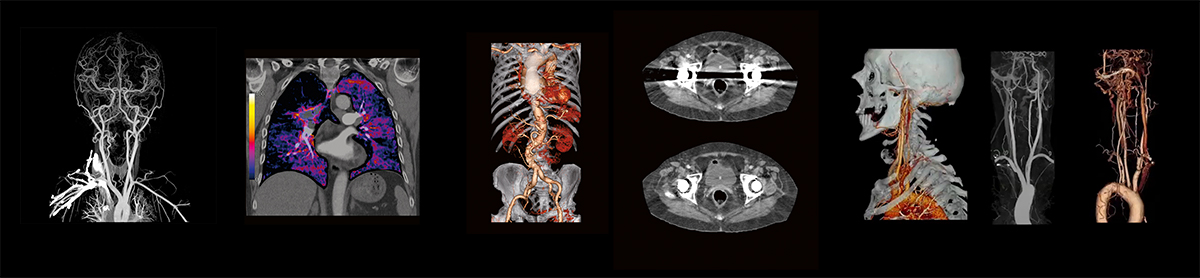

სწორედ ამიტომ, აკადემიკოს ვახტანგ ბოჭორიშვილის კლინიკაში წარმოდგენილია კომპიუტერული ტომოგრაფი Aquilion Lightning 160 slice - Canon Medical Systems-ის მიერ შექმნილი ტექნოლოგიური პლატფორმა, რომელიც აერთიანებს ხელოვნურ ინტელექტს, ინოვაციურ სისტემასა და სკანირების სხვადასხვა რეჟიმებს.

აღნიშნული CT სისტემა განკუთვნილია მაღალი დატვირთვის მქონე კლინიკებისთვის, სადაც მნიშვნელოვანია არა მხოლოდ ტომოგრაფიის შედეგად მიღებული გამოსახულების ხარისხი და სანდოობა, არამედ კვლევის სისწრაფეც.

Aquilion Lightning 160 slice კომპიუტერული ტომოგრაფი წარმოადგენს თანამედროვე კომპიუტერული ტომოგრაფიის ევოლუციას, სადაც ერთ სისტემაშია გაერთიანებული გამოსახულების მაღალი ხარისხი, ხელოვნური ინტელექტი და გამოსხივების დონის ოპტიმიზაცია. აღნიშნული აპარატი არ არის მხოლოდ სკანირებისთვის განკუთვნილი მოწყობილობა - იგი წარმოადგენს სრულფასოვან ტექნოლოგიურ ეკოსისტემას, რომელიც შექმნილია თანამედროვე რადიოლოგიური პრაქტიკის მოთხოვნების სრულად დასაკმაყოფილებლად.

Aquilion Lightning 160 slice აერთიანებს PUREVISION Detector Technology-ს, რომელიც იყენებს 0.5 მმ სისქის დეტექტორულ ელემენტებს, შედეგად კი იქმნება 29%-ით უფრო თხელი შრეები, სხვა აპარატებთან შედარებით. ასეთი კონფიგურაცია იძლევა იზოტროპული გამოსახულებების მიღების საშუალებას ნებისმიერ სიბრტყეში.იზოტროპული გამოსახულების უპირატესობებია:

Enhanced Iodine Imaging - მრავალფაზიანი კვლევების გაფართოებული შესაძლებლობები

- ორგანოთა პერფუზიის შეფასება;

- მცირე და სუსტად გამოხატული დაზიანებების უკეთესად დანახვა;

- სისხლძარღვების მკაფიო გამოსახულების მიღება.